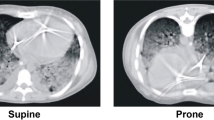

Within 1 day, intratracheal instillation of bleomycin leads to quantitative and qualitative surfactant abnormalities linked with microatelectases during mechanical ventilation with positive end-expiratory pressure (PEEP) below 5 cmH2O, so that these lungs can be considered as lungs at risk for propagation of surfactant dysfunction and injury progression during mechanical ventilation (Knudsen et al. 2018; Lutz et al. 2015). Hence, the present study investigates the effects of early bleomycin-induced lung injury in combination with mechanical ventilation with different PEEP levels on the ultrastructure of the blood–gas barrier and the AE2 cells including the intracellular surfactant pool. The PEEP level determines whether bleomycin-injured lungs exhibit microatelectases or not. Therefore, we opted to ventilate the lungs with PEEP = 1 cmH2O, where microatelectases are present, or at PEEP = 5 cmH2O, where microatelectases are nearly absent. Since mechanical ventilation of lungs suffering from microatelectases would induce alveolar overdistension due to alveolar interdependence (Albert et al. 2019, 2020; Knudsen et al. 2018), we hypothesize that PEEP = 1 cmH2O ventilation of bleomycin-injured lungs will exhibit abnormalities of intracellular surfactant pool and interstitial abnormalities that demarcate injury progression within alveolar septa.

Qualitative investigations of the interalveolar septa demonstrated thin blood–gas barriers throughout the healthy (H) study groups, independent of mechanical ventilation or not (Fig. 1). The alveolar epithelial cells were slim at the thin side of the blood–gas barrier with hardly any signs of injury such as clearance of the cytoplasmic ground substance, blebbing or fragmentation. The same was the case regarding the endothelial cells. On the thick side of the blood–gas barrier, which usually contributes 50% of the blood–gas barrier and where the epithelial and endothelial basal laminae are separated by interstitial tissue, the layers of the blood–gas barrier were also compact without any signs of an interstitial oedema. In contrast, epithelial injury could occasionally be observed in all 3 bleomycin groups (B). In B/no_ventil, swollen alveolar epithelial cells were seen on both the thin and the thick side of the blood–gas barrier. The interstitium between endothelial cells and epithelial cells on the thick side did not substantially differ from the healthy lungs and could be described as being relatively compact. The endothelial cells did not show any ultrastructural signs of injury. After mechanical ventilation with PEEP = 1 cmH2O in the bleomycin-injured lungs, denudations of the epithelial basal lamina were the most severe ultrastructural feature of injury. Also, the interstitial tissue between epithelial and endothelial basal laminae was widened and the collagen fibrils appeared to be torn apart and therefore less compact. Also in B/PEEP5, widening of the interstitial space within interalveolar septa could be observed. However, these abnormalities were by far not that severe as in B/PEEP1 and denudations of the epithelial basal lamina were virtually absent.

Based on these qualitative observations, we quantified the composition of the interalveolar septa and the thickness of the blood–gas barrier. The data are summarized in Table 2 and visualized in part in Fig. 2. The statistical analyses took the factors bleomycin pre-treatment and the mechanical ventilation into consideration. Neither bleomycin pre-treatment nor mechanical ventilation had a significant effect on the volume of AE cells within interalveolar septa, V(AE,sep). The surface area of air-covered AE1 cells, S(AE1,sep), was reduced by bleomycin pre-treatment; while ventilation did not show an effect. The surface area of AE2 cells covered by air S(AE2,sep) was unaffected by bleomycin pre-treatment and mechanical ventilation. The absolute volume of the interstitium within interalveolar septa was significantly increased due to bleomycin pre-treatment (Table 2). The adjustment of the p value by means of Tukey post hoc test illustrated a significantly higher V(inter,sep) in B/PEEP1 compared to B/PEEP5; while, there were no differences between B/no-ventil and B/PEEP5 (Fig. 2a). Since the interstitium consists of interstitial cells (IC) and extracellular matrix (ECM) which can further be distinguished in collagen fibrils (col) and ECM other than collagen fibrils (restECM), the volumes of these components were analyzed further. Neither bleomycin pre-treatment nor mechanical ventilation had an effect on V(ECM,sep) (Table 2). On the other hand, bleomycin-induced lung injury resulted on day 1 after instillation already in an increase in the volume of interstitial cells (Fig. 2b; V(IC,sep)) and this increase was most pronounced in B/PEEP1 so that the increase in V(inter,sep) at the organ scale was primarily a consequence of an increase in the volume of interstitial cells within septa rather than an increase in the volume of extra cellular matrix. Finally, the capillary network within the interalveolar septa was analyzed. This included the quantification of the volumes of endothelial cells (V(endo,sep)) and capillary lumen (V(caplumen,sep)) as well as the surface area of the endothelial cells (S(endo,sep)). None of these parameters was affected by bleomycin pretreatment or mechanical ventilation. The volume of the blood–gas barrier and its surface areas at the air and blood side were used to determine the arithmetic mean thickness of the blood–gas barrier \(\tau\)(bgb). \(\tau\)(bgb) was increased as a result of the bleomycin pre-treatment and this increase was most pronounced in B/PEEP1 so that the Tukey post hoc test for adjustment of the p level revealed that, within the B group, \(\tau\)(bgb) was significantly higher in B/PEEP1 compared to B/PEEP5 (Fig. 2c). Dividing the blood–gas barrier into its components, alveolar epithelium, interstitium and endothelium, reveals that the increase in barrier thickness was mainly a result of the increase in the thickness of the interstitial layer \(\tau\)(inter). This alteration was most pronounced in the bleomycin groups where \(\tau\)(inter) was elevated in B/PEEP1 compared to B/PEEP5 (Fig. 2d). With regard to the thickness of the endothelial layer \(\tau\)(endo), there was a significant effect assigned to the bleomycin pretreatment but the Tukey post hoc test did not reveal differences between the subgroups.